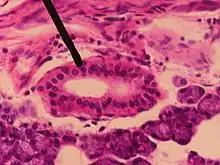

Striated duct in parotid gland

A striated duct (Pflüger's ducts) is a gland duct which connects an intercalated duct to an interlobular duct. It is characterized by the basal infoldings of its plasma membrane, characteristic of ion-pumping activity by the numerous mitochondria.[8][9] Along with the intercalated ducts, they function to modify salivary fluid by secreting HCO3 and K+ and reabsorbing Na+ and Cl using the Na-K pump and the Cl-HCO3 pump, making the saliva hypotonic.

Their epithelium can be simple cuboidal or simple columnar.[10]

Striated ducts are part of the intralobular ducts.

They are found in the submandibular gland,[11][12] sublingual duct, and the parotid gland, but are more developed in the parotid gland.[13]

They are not present in pancreas.